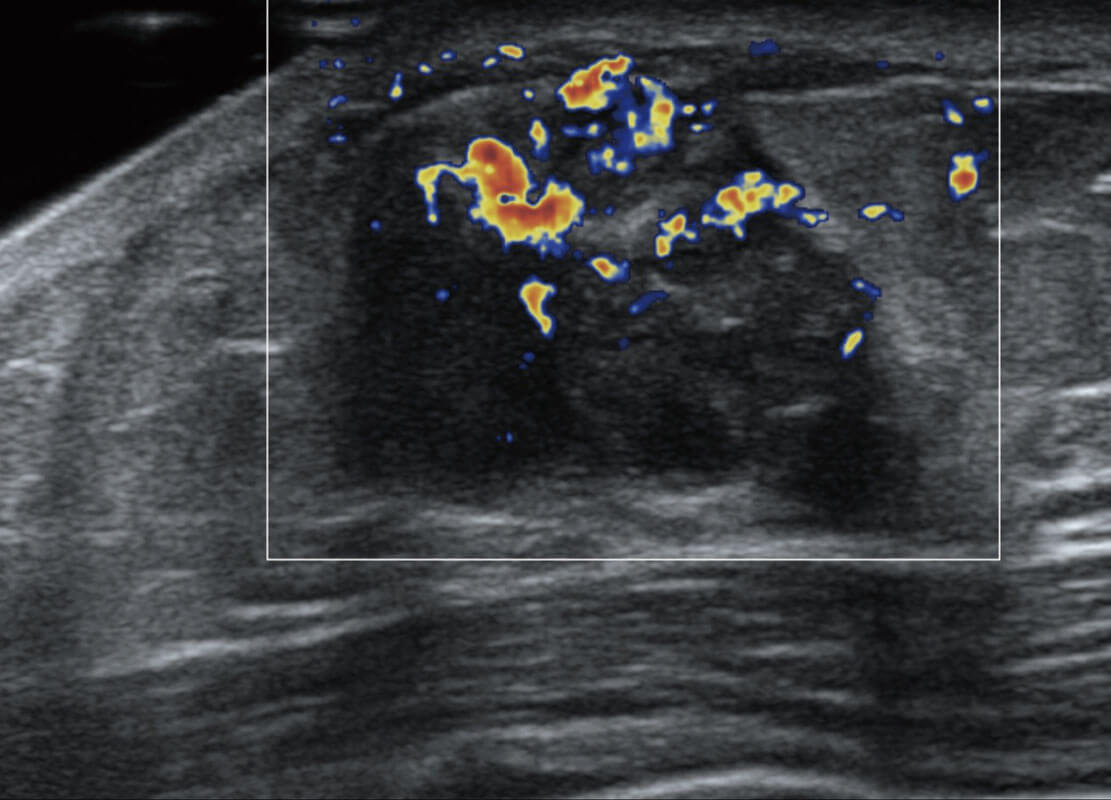

P60搭载宽频带线阵探头、宽景成像、弹性成像技术,为您提供乳腺应用方案。P60支持高频相控阵探头、线阵探头、腹部高频探头、腹部微凸探头等,丰富的探头群搭载敏感的彩色血流成像,适用于新生儿多种脏器检测要求,满足新生儿筛查需求。

乳腺导管癌

乳腺癌显微血流

新生儿肝血管癌